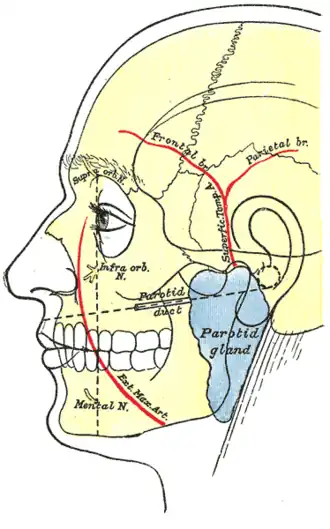

Na anatomia humana, a artéria temporal superficial é uma das artérias principais da cabeça. Surge da artéria carótida externa e bifurca na artéria temporal superficial e na artéria maxilar.

Começa na substância da glândula parótida, atrás do pescoço e da mandíbula, e cruza em cima da raiz posterior do processo zigomático do osso temporal; aproximadamente 5 cm. sobre este processo divide em dois ramos, um frontal e um parietal.

Como cruza o processo zigomático, está coberta pelo músculo anterior auricular, e por um fascia denso; é cruzada pelo ramo temporal e zigomático do nervo facial e uma ou duas veias, e é acompanhado pelo nervo aurículo-temporal que fica atrás disto.

A artéria temporal superficial faz anastomose com a artéria supra-orbital da artéria carótida interna (entre outras).